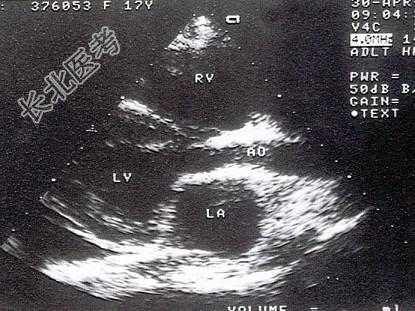

- 单项选择题该病例最可能的诊断为 ( )

A、主动脉瓣上膜性狭窄

B、主动脉瓣上缩窄

C、肥厚性心肌病

D、瓣上环形狭窄

E、高血压病